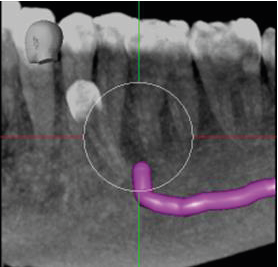

From a surgical perspective, the root of the supernumerary tooth is straight and its apex contacts the ID canal at the point at which the mental canal is given off (images 5 and 6). The only potential risk would be with downward pressure. In a surgical context there is a potential risk with any applied downward pressure.

5. Oblique mesio-distal cross-section through the supernumerary tooth, showing the neurovascular canal in contact with its root apex (mental foramen arrowed).